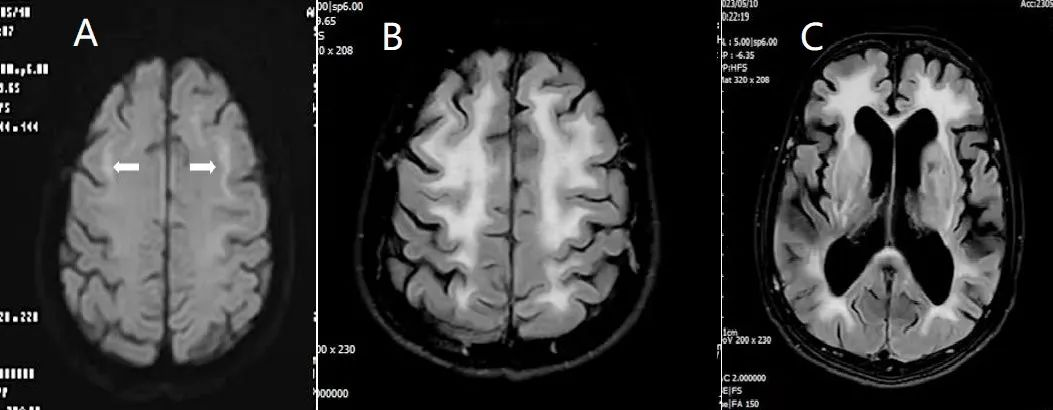

▲双侧脑白质及皮髓交界区

对称性异常信号影

患者入院后,通过询问相关病史,详细查体,考虑患者并非简单的帕金森病或帕金森综合症,而是累及中枢神经、周围神经、自主神经多系统病变。在何锦照副院长的带领主持下,由神经内科三区马国奋主任医师、童永堂主治医师、神经内科电生理室马国重副主任医师、病理科温达雄主任医师、影像科黎艳主任医师、普外科司丕成主任医师组成的多学科会诊小组对患者病情进行了全面、细致评估,拟定方案,进行针对性的肌电图、头部影像学、皮肤活检、基因测序等检查,最终明确诊断为神经元核内包涵体病(NIID)。